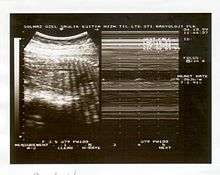

A biophysical profile (BPP) is a prenatal ultrasound evaluation of fetal well-being involving a scoring system,[1] with the score being termed Manning's score.[2] It is often done when a non-stress test (NST) is non reactive, or for other obstetrical indications.